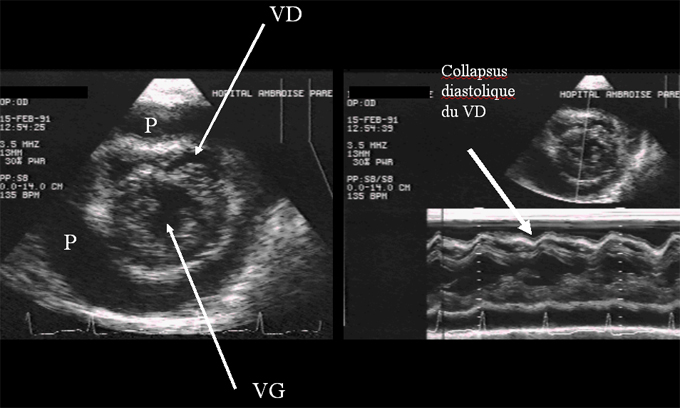

Figure 12 : Short-axis examination of the right (VD) and left (VG) ventricles in a patient presenting pericardial effusion (P). The diastolic collapse of the RV is visible both on the two-dimensional view (left) and in M-mode (right).